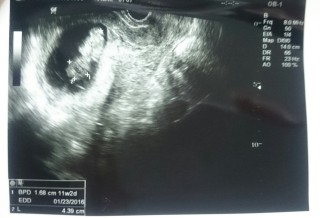

頭殿長は4センチを超えて、順調に育っていました(^^)エコーで映した瞬間、手足をバタバタと動かしていて可愛かったです。